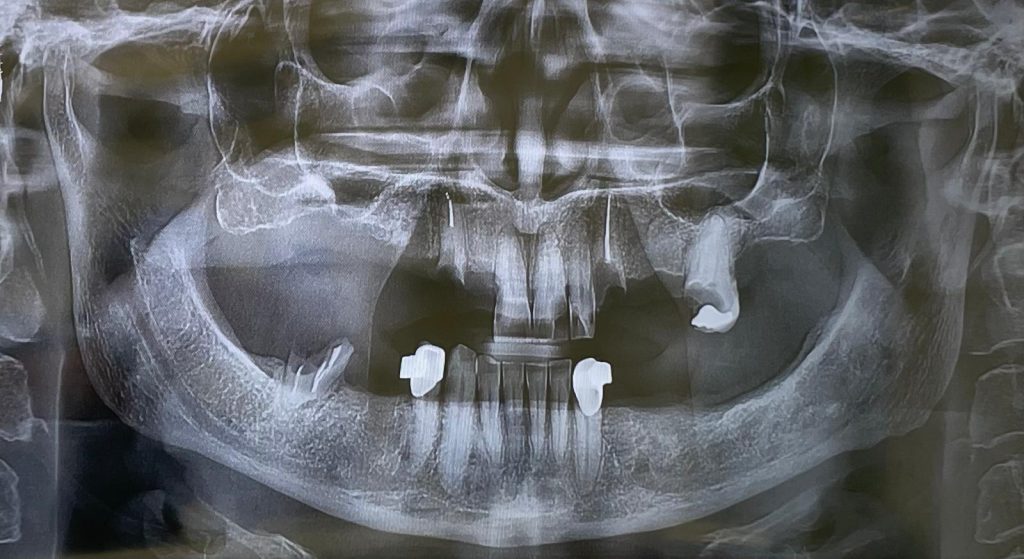

Questa settimana vi presento un caso di riabilitazione immediata dell’arcata superiore eseguita in chirurgia computer guidata con l’utilizzo di dime scomponibili.

L’intervento ha previsto l’estrazione degli elementi dentari, l’inserimento di 5 impianti nell’arcata superiore, il montaggio delle torrette provvisorie e la ribasatura del provvisorio nel cavo orale.